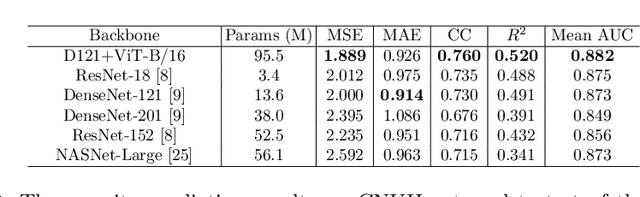

Abstract:Developing a robust algorithm to diagnose and quantify the severity of COVID-19 using Chest X-ray (CXR) requires a large number of well-curated COVID-19 datasets, which is difficult to collect under the global COVID-19 pandemic. On the other hand, CXR data with other findings are abundant. This situation is ideally suited for the Vision Transformer (ViT) architecture, where a lot of unlabeled data can be used through structural modeling by the self-attention mechanism. However, the use of existing ViT is not optimal, since feature embedding through direct patch flattening or ResNet backbone in the standard ViT is not intended for CXR. To address this problem, here we propose a novel Vision Transformer that utilizes low-level CXR feature corpus obtained from a backbone network that extracts common CXR findings. Specifically, the backbone network is first trained with large public datasets to detect common abnormal findings such as consolidation, opacity, edema, etc. Then, the embedded features from the backbone network are used as corpora for a Transformer model for the diagnosis and the severity quantification of COVID-19. We evaluate our model on various external test datasets from totally different institutions to evaluate the generalization capability. The experimental results confirm that our model can achieve the state-of-the-art performance in both diagnosis and severity quantification tasks with superior generalization capability, which are sine qua non of widespread deployment.

Abstract:Under the global COVID-19 crisis, developing robust diagnosis algorithm for COVID-19 using CXR is hampered by the lack of the well-curated COVID-19 data set, although CXR data with other disease are abundant. This situation is suitable for vision transformer architecture that can exploit the abundant unlabeled data using pre-training. However, the direct use of existing vision transformer that uses the corpus generated by the ResNet is not optimal for correct feature embedding. To mitigate this problem, we propose a novel vision Transformer by using the low-level CXR feature corpus that are obtained to extract the abnormal CXR features. Specifically, the backbone network is trained using large public datasets to obtain the abnormal features in routine diagnosis such as consolidation, glass-grass opacity (GGO), etc. Then, the embedded features from the backbone network are used as corpus for vision transformer training. We examine our model on various external test datasets acquired from totally different institutions to assess the generalization ability. Our experiments demonstrate that our method achieved the state-of-art performance and has better generalization capability, which are crucial for a widespread deployment.